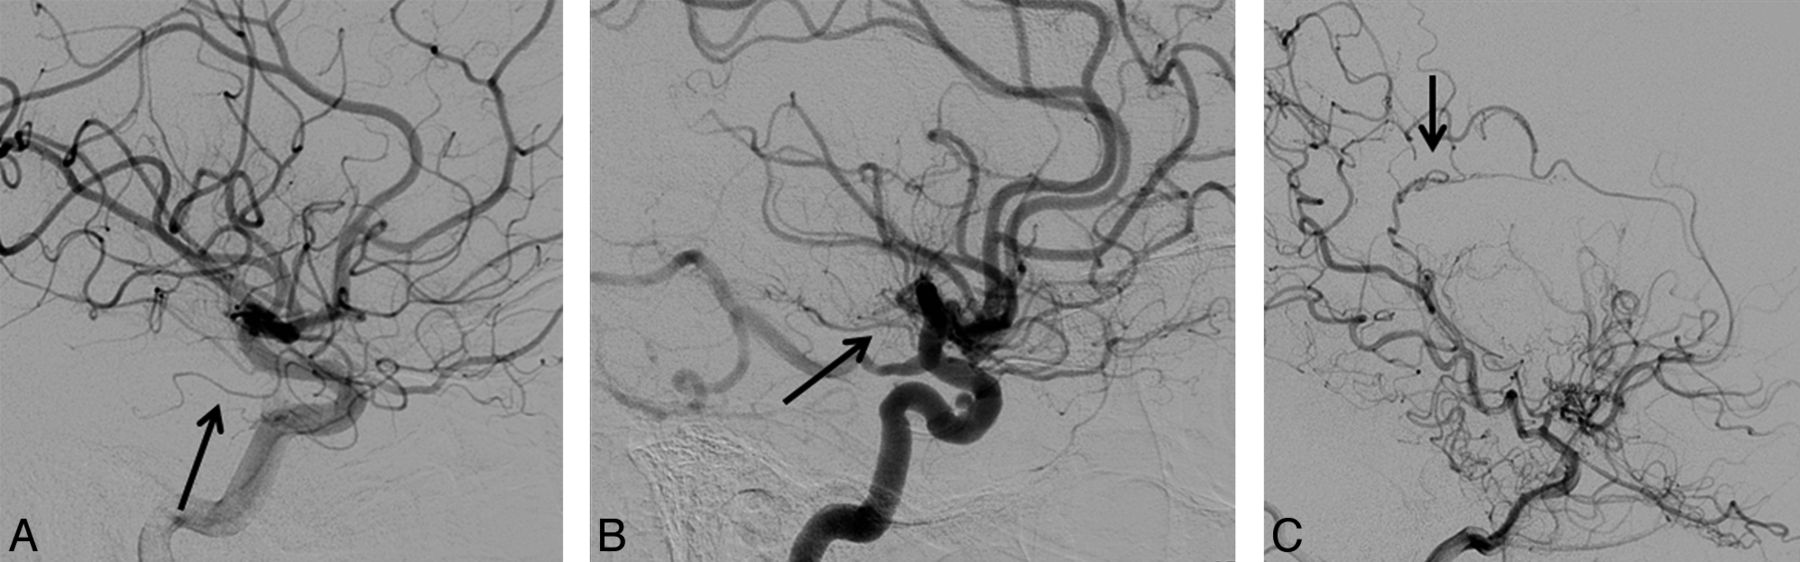

AchoA grades are shown in Fig 6. Table 3 shows the distribution of AchoA grades by imaging findings. There was a significant association between the AchoA classification and mSS (P = .02). The OR of having a more severe mSS classification was 2.76 times higher (95% CI, 0.57–13.24) for hemispheres with grade I AchoA versus control subjects (P = .21), and the OR increased to 17.2 (95% CI, 2.26–131.1) when comparing grade II AchoA with control subjects (P = .01). In 9 hemispheres, the AchoA was occluded due to ICA occlusion proximal to the AchoA origin and lack of collateral AchoA filling via posterior collaterals. All such hemispheres were mSS IV; none had hemorrhage and 5 of 9 had infarcts. All hemispheres with hemorrhage (4 of 78) had AchoA grade 2, and none had P1 steno-occlusive findings.

Lateral projections from DSA in 3 patients with Moyamoya disease, with the AchoA identified by the arrow. A, The AchoA appears normal without proliferative vessels (stage zero). B, The AchoA is thickened with distal branching (stage I). C, The AchoA is dilated, and abnormal branches serve as collaterals (stage II).